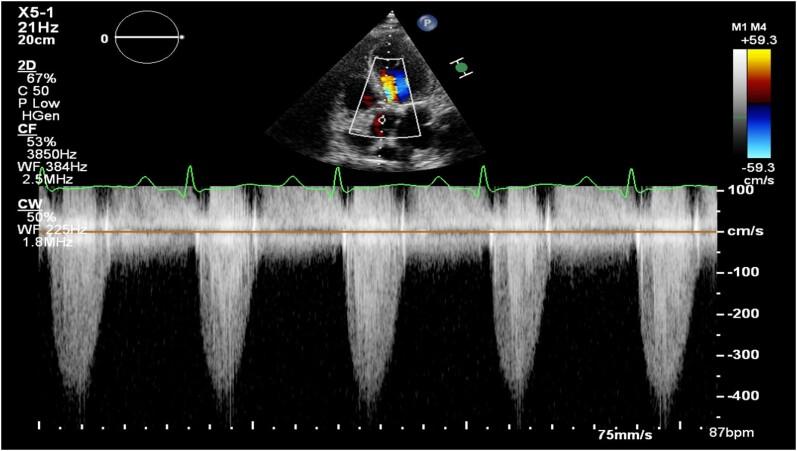

Left ventricular assist devices (LVADs) are increasingly utilized in cardiogenic shock and high-risk percutaneous coronary interventions (PCIs). These devices aspirate and expel blood from the left ventricle (LV) into the aorta, consequently reducing left ventricular end-diastolic pressure (LVEDP). We report a case of unexpected LVEDP rise under LV-to-aorta LVAD in the context of transcatheter aortic valve implantation (TAVI) and concomitant multi-vessel PCI.

A patient with acute heart failure, severely depressed systolic LV function, severe aortic stenosis, and multi-vessel coronary artery disease underwent TAVI and concomitant PCI under pulsatile LVAD. Notably, the patient experienced unexpected shortness of breath and elevated LVEDP while under LVAD, which normalized immediately upon LVAD removal.

Pulsatile LVAD enhances cardiac output by providing pulsatile support through a percutaneous bi-directional flow catheter. Despite expectations of reduced LVEDP and improved myocardial oxygen supply under LVAD support, we observed high LVEDP and clinical complaints of shortness of breath following TAVI and multi-vessel PCI. This case illustrates that an LVAD across the aortic valve may immobilize aortic leaflets and generate acute aortic regurgitation.